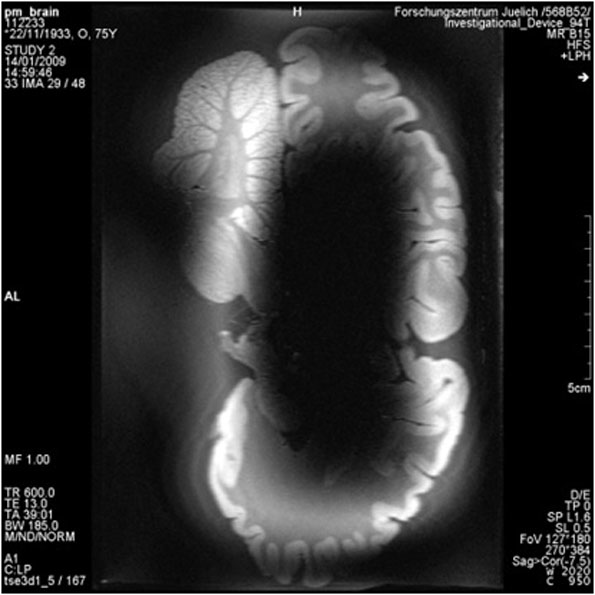

The new generation of ultra-high-field devices, with B-fields of 7 T, 9.4 T, or higher, introduces a new set of problems for MRI designers to consider. High-field devices produce images with much better resolutions than their low-field counterparts (Fig. 1).1 But they also operate at higher frequencies and produce higher power absorption in the human body; while the signal-to-noise ratio (SNR) improves linearly over frequency, the SAR is proportional to the square of the frequency, and this can increase heating effects substantially.

1. This is a comparison of the images from low- and high-field MRI systems, showing a cross-section of a hippocampus.